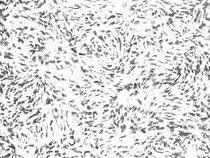

(2)镜下变化:瘤细胞呈圆形或多角形,形态相当一致,胞浆很少,染色浅,胞膜不清楚。细胞核呈圆形或椭圆形,大小比较一致,颗粒细,分布均匀,核分裂相多见。瘤组织内细胞丰富,细胞排列成巢状,偶见20个左右瘤细胞呈环形排列,形成“假菊形团”结构。瘤组织常有大片坏死。在肿瘤周围可有新骨形成,为反应性新生骨,而不是肿瘤本身成分。